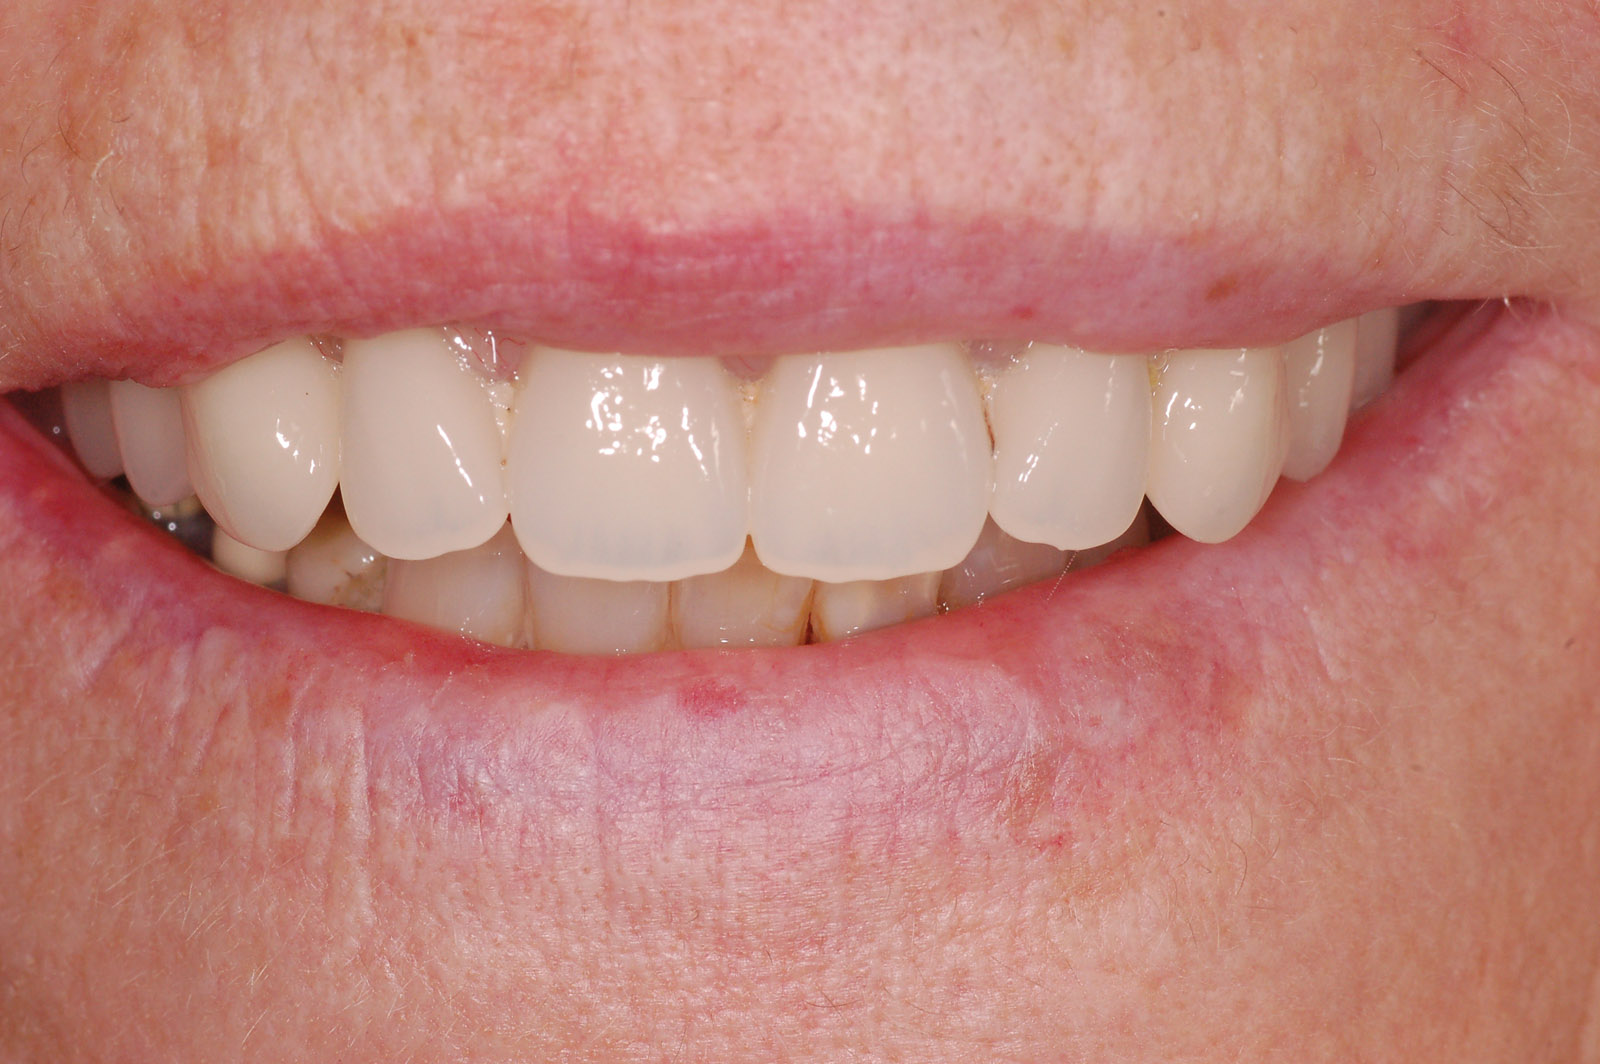

Immediately following surgery, the patient is advised to adhere to a soft diet and not to remove the denture for two weeks, but keep it very clean by brushing and using a Waterpik. The patient was then reviewed at appropriate intervals to assess healing and an OPG radiograph taken as a baseline record (Figures 11,12,13).

The patient was very pleased with the final aesthetic result, which improved her confidence when talking to people. She was once again able to enjoy chewing food without discomfort (Figure 14).